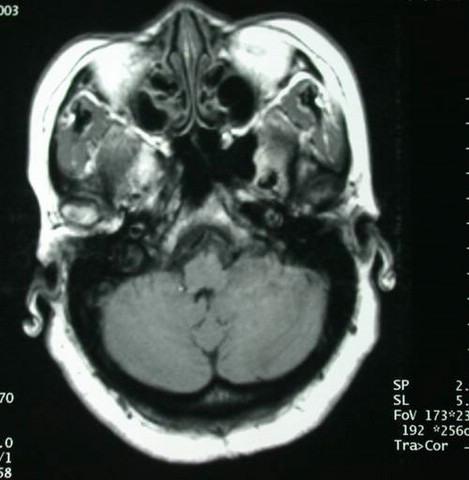

男性,20岁,因头痛,伴剧烈恶心、呕吐3天入院。查MRI提示四脑室占位病变。如下: